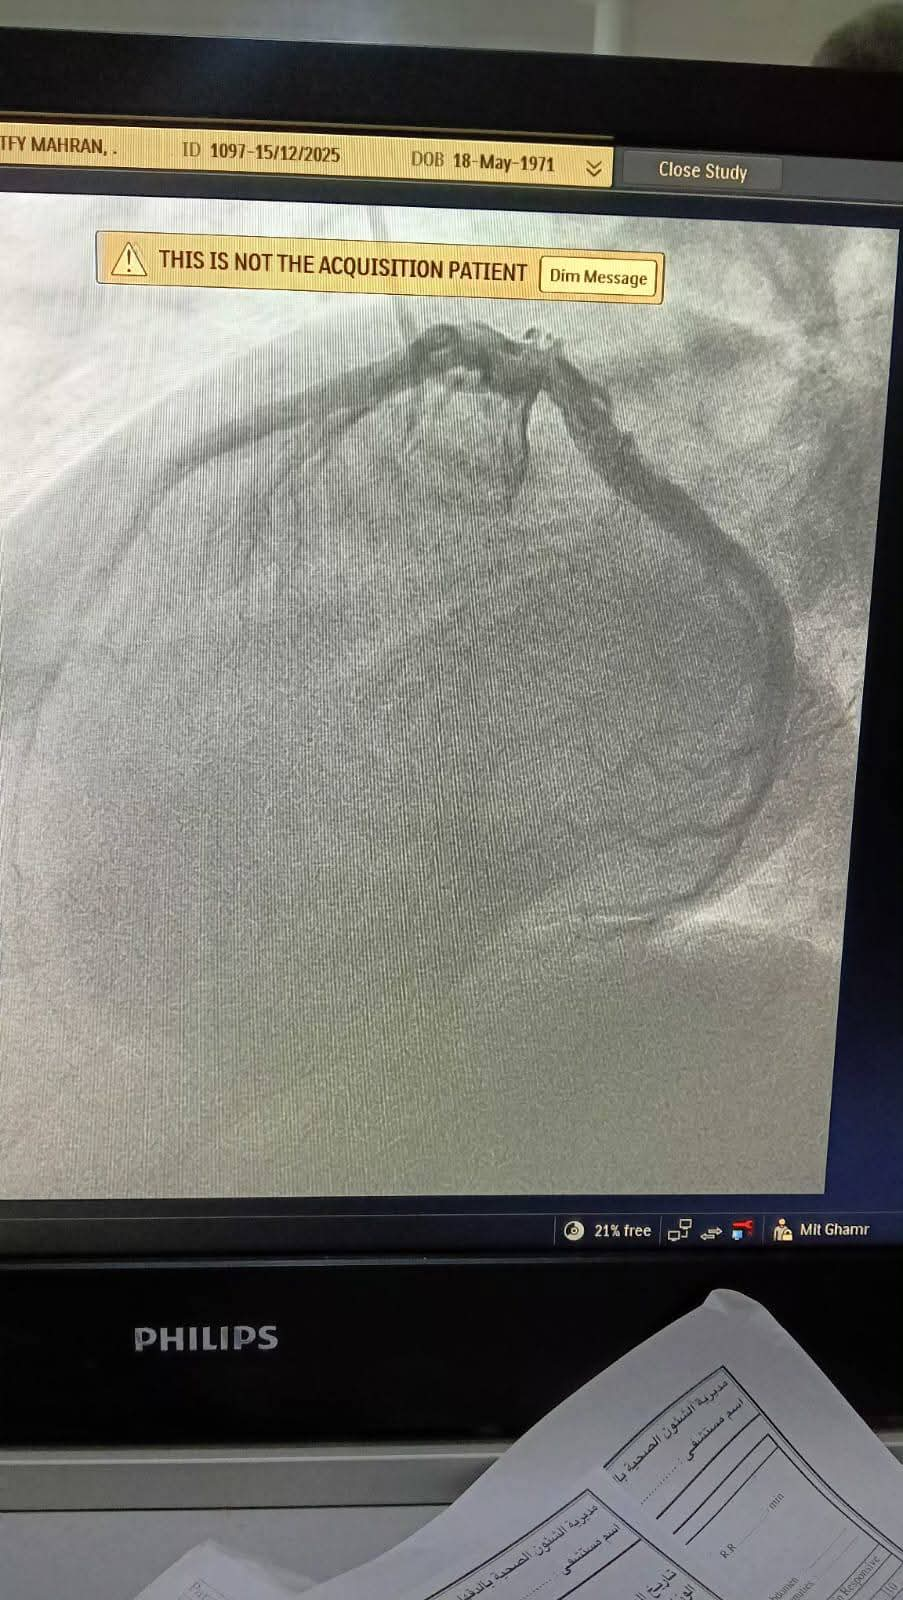

وبمجرد وصول المريضة إلى مستشفى ميت غمر العام عن طريق الإسعاف، تم إجراء الفحوصات والتحاليل اللازمة بشكل عاجل، وتجهيزها للتدخل الطبي، حيث جرى إدخالها لإجراء قسطرة قلبية تشخيصية خلال وقت قياسي، كشفت عن وجود جلطة بالشريان التاجي أثرت على تدفق الدم إلى عضلة القلب.

وعلى الفور، تم التعامل مع الحالة وإزالة الجلطة بنجاح، مما أدى إلى تحسن سريان الدم واستقرار الحالة الصحية للمريضة، وتم نقلها إلى العناية القلبية لاستكمال العلاج والمتابعة حتى خروجها بحالة جيدة.